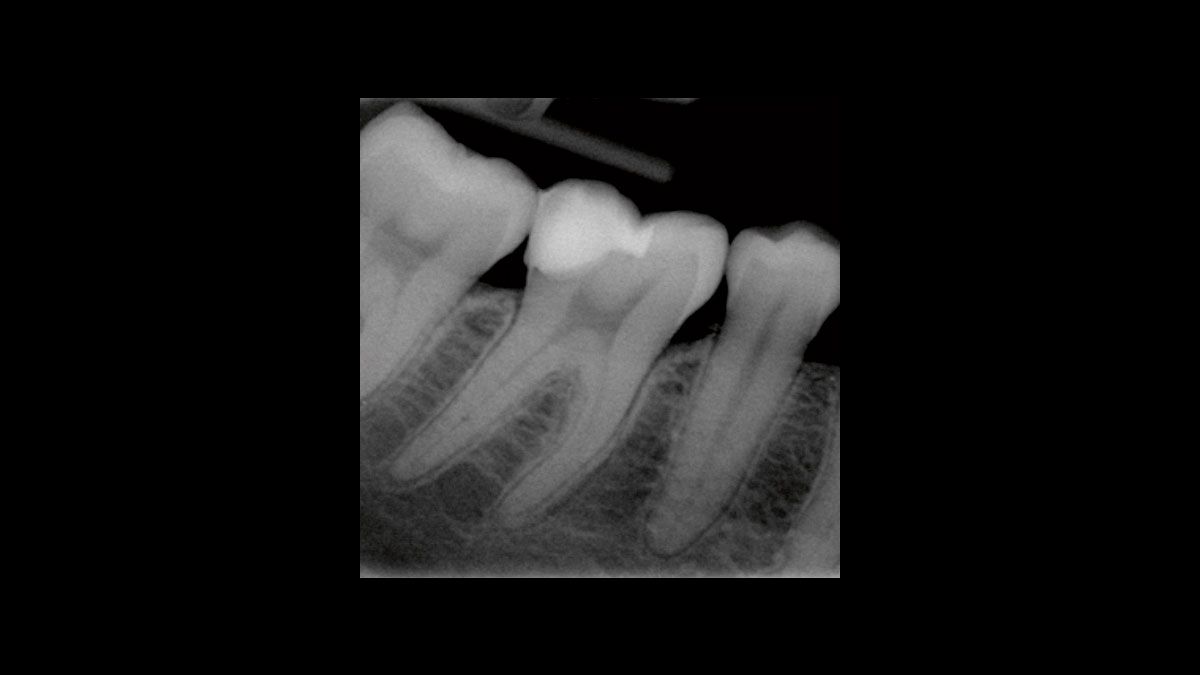

Endodontics

The following applications are presented in the videos and images:

• Endodontic germ reduction

• Gangrene germ reduction

Endodontic germ reduction